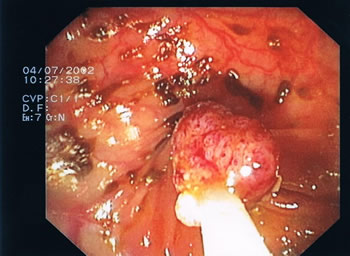

Endoskopische Bilder. Das Darmlumen innerhalb der einzelnen Darmabschnitte kann eher rundlich, leicht eingeengt oder dreieckförmig aussehen, entsprechend des anatomischen Aufbaus (s. Abb.1-4). Grundsätzlich gibt es verschiedene Arten von Polypen mit unterschiedlichen Konfigurationen und von verschiedener Größe. Kugelig(Abb.6) mit schmaler Verbindung zur Darmwand, hügelig mit breiter Basis, muschelförmig, die sich häufig an eine Querfalte anschmiegen, gestielte Polypen, die über einen Stiel mit der Darmwand verwachsen sind und sessile Polypen (Abb.5), die breitbasig auf der Darmwand aufsitzen. Der Übergang zum Dünndarm (Ileocaecal-Klappe) kann des Öfteren ein polypöses Aussehen vortäuschen (Abb.4).

Unentdeckte Polypen können nach vielen Jahren in ein Karzinom übergehen (Abb. 8).